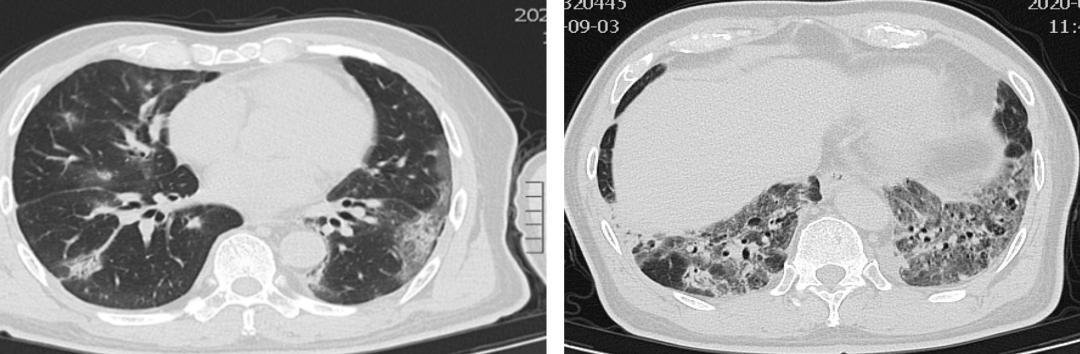

【图1】入院前胸部CT

【图2】入院后一周CT。使用40-60mg甲强龙同时,呼吸困难缺氧进行性加重。双肺磨玻璃渗出明显增多,胸膜下及双下肺网格影增多。